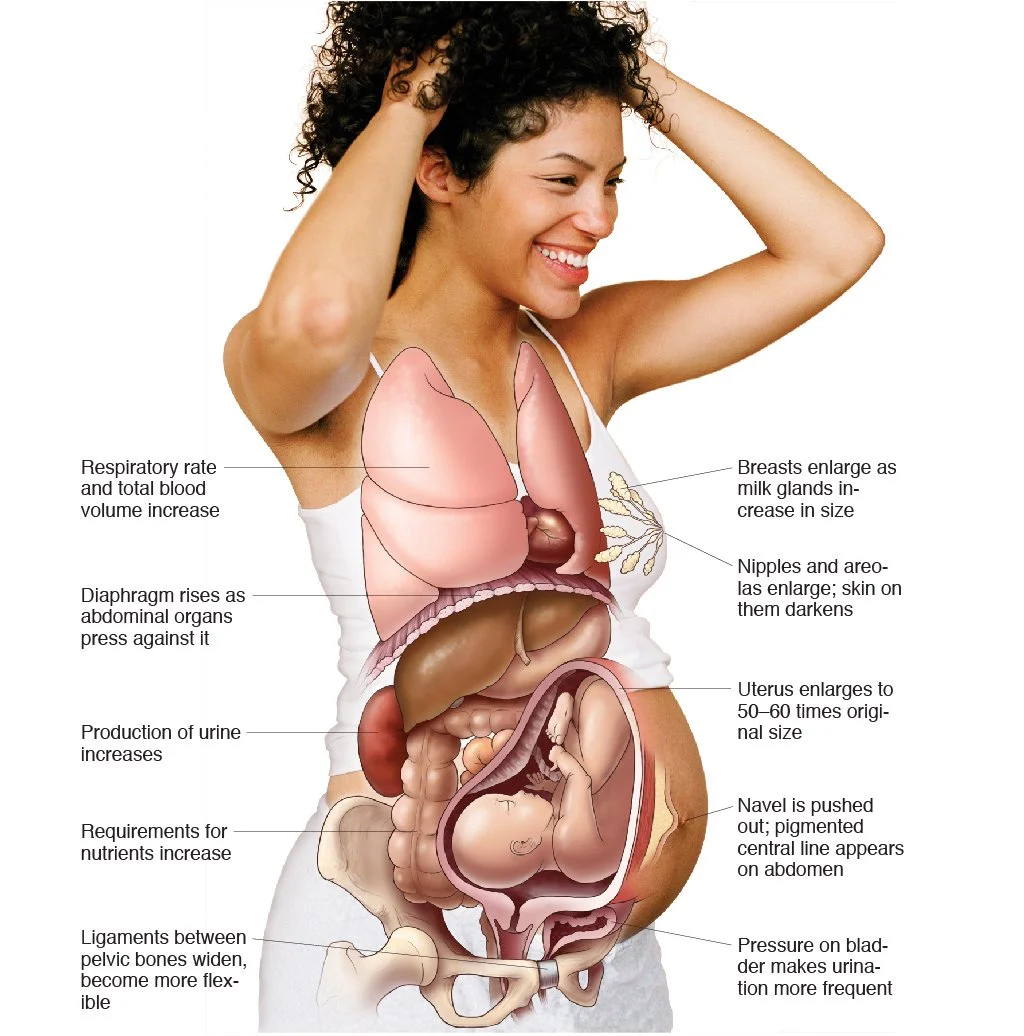

Medical Illustration

All images are works made for hire and are the exclusive property of the client. These are shown as sample purposes of my work only. For licensable work, please see my Illustration Services page.

Medical Illustrator for Precision Graphics, Lachina, and Human Kinetics Publishing (current)

Contract freelancer for many others, some examples of my work below.